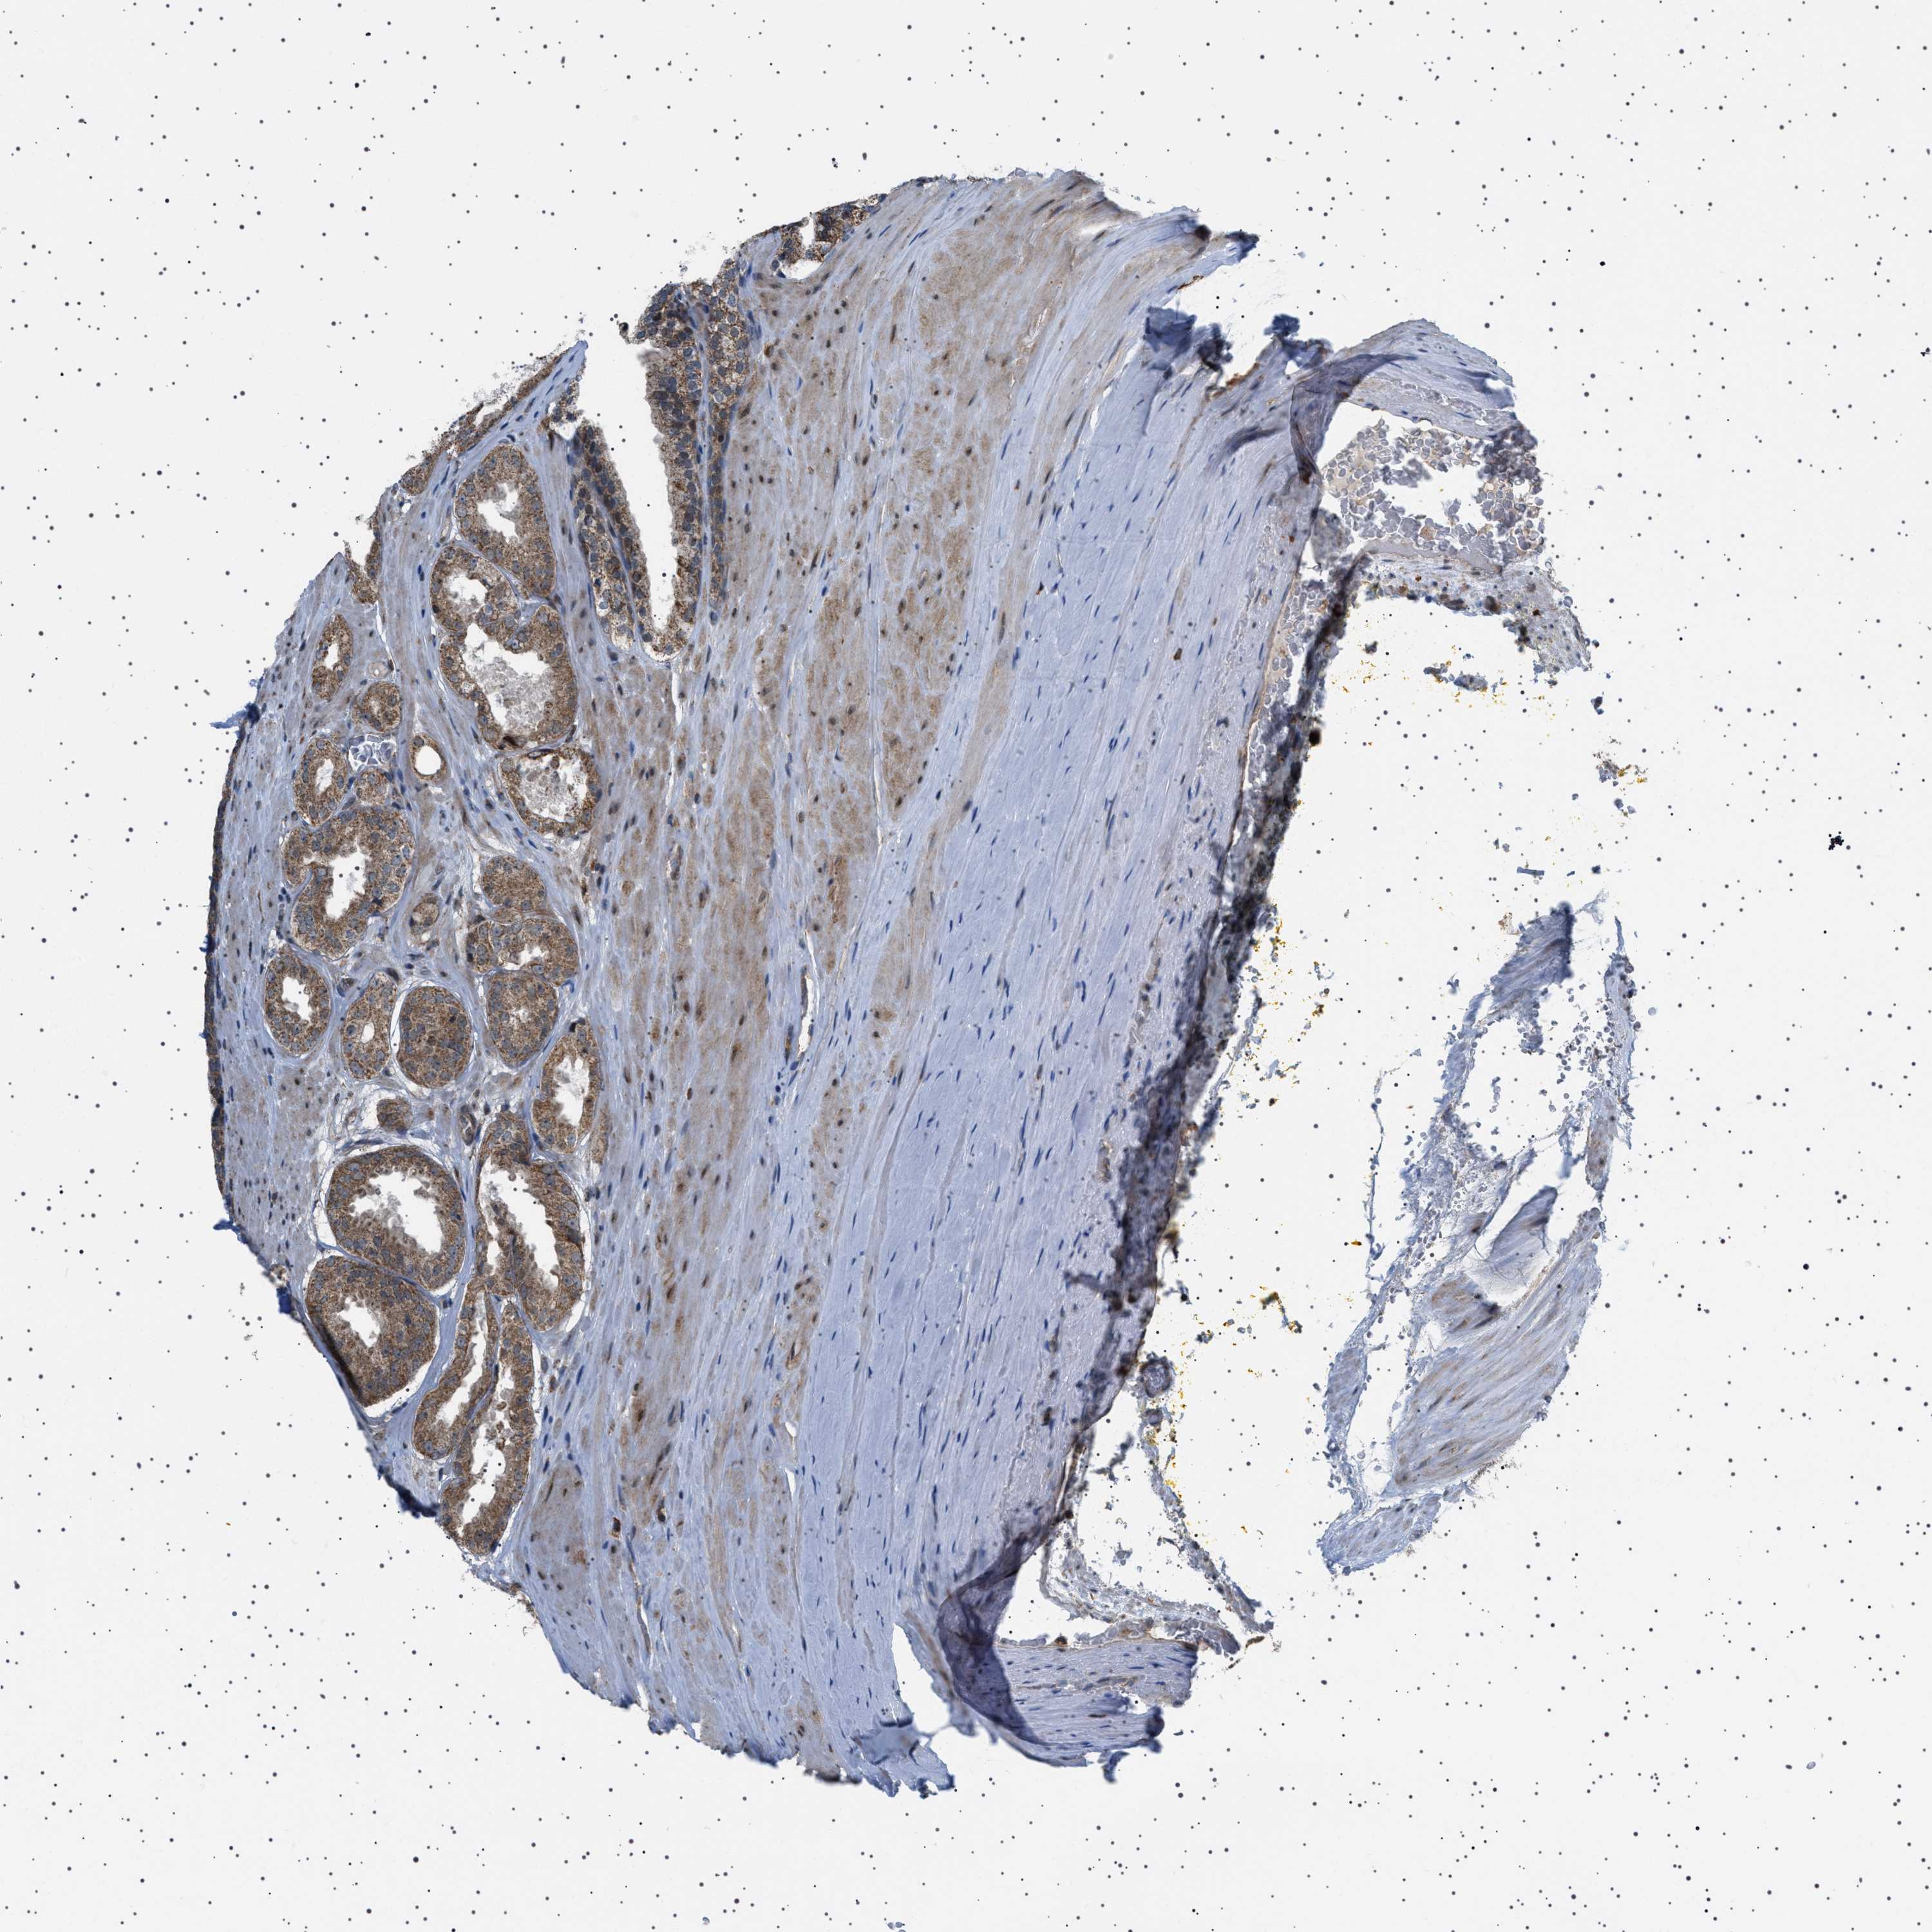

PROSTATE CANCER - Protein expressioni

A mouse-over function shows sample information and annotation data. Click on an image to view it in a full screen mode. Samples can be filtered based on level of antibody staining by selecting one or several of the following categories: high, medium, low and not detected. The assay and annotation is described here.

Note that samples used for immunohistochemistry by the Human Protein Atlas do not correspond to samples in the TCGA dataset.

Antibody stainingi

Antibody staining in the annotated cell types in the current human tissue is reported as not detected, low, medium, or high, based on conventional immunohistochemistry profiling in selected tissues. This score is based on the combination of the staining intensity and fraction of stained cells.

Each image is clickable and will lead to virtual microscopy that enables deeper exploration of all samples and also displays staining intensity scores, fraction scores and subcellular localization as well as patient and tissue information for each sample.

Antibody HPA017214

Staining

High

Medium

Low

Not detected

Intensity

Strong

Moderate

Weak

Negative

Quantity

>75%

75%-25%

<25%

None

Location

Nuclear

Cytoplasmic/membranous

Cytoplasmic/membranous,nuclear

Adenocarcinoma, High grade

Adenocarcinoma, Low grade